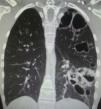

Chest computer tomography showed cystic bronchiectasis and cavitations in the left lower and upper lobes (Fig. 2). X-rays of wrists and legs showed periosteal reaction along the metacarpals, distal radius, ulna, tibia and fibula (Fig. 3) but not acro-osteolysis of the distal phalanges of the hands and feet. Human immunodeficiency virus antibody test was negative. Pharmacologic therapy with nonsteroidal anti-inflammatory drugs was effective in relieving pain from hypertrophic osteoarthropathy (HOA) during his hospital stay and after 3 months of follow-up.